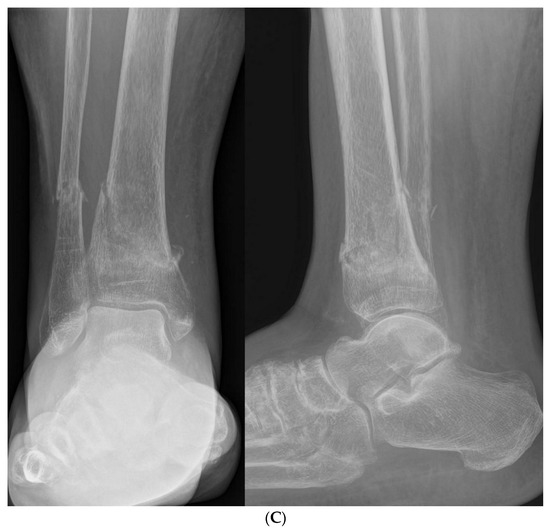

Basic Differences and Most Common Findings in Ultrasound Examinations of Musculoskeletal System in Children: A Narrative Literature Review

We present basic differences in the musculoskeletal ultrasound examinations between adults and children. Examiners who deal with adults on a daily basis have shared concerns about examining children. Such concerns may arise from the different approach to child ultrasounds, but they also come [...] Read more.

We present basic differences in the musculoskeletal ultrasound examinations between adults and children. Examiners who deal with adults on a daily basis have shared concerns about examining children. Such concerns may arise from the different approach to child ultrasounds, but they also come from differences in anatomical characteristics according to developmental age. We discuss the presence of growth plates, as well as non-mineralized parts of the bones. We also refer to the pathologies most often found in ultrasounds in early developmental stages. In the PubMed database, the set of keywords: “msk ultrasound in children”, “pediatric msk sonoanatomy”, “coxitis fugax”, “pediatric Baker’s cyst”, “Baker’s cyst ultrasonography”, “bone septic necrosis in ultrasonography”, “ultrasonography in juvenile idiopathic arthritis”, and “ultrasonography in juvenile spondyloarthropathies”, was used to identify a total of 1657 results, from which 54 was selected to be included in the article. We discuss the problem of osteochondritis dissecans, Osgood-Schlatter disease, examples of ligament injuries (especially in relation to the knee and ankle joints), exfoliation of growth cartilages, osteochondroma, exudates and inflammations affecting joints, and Baker’s cysts. In this way, we have collected useful information about the most common diseases of the musculoskeletal system in children. Full article

Show Figures

Figure 1